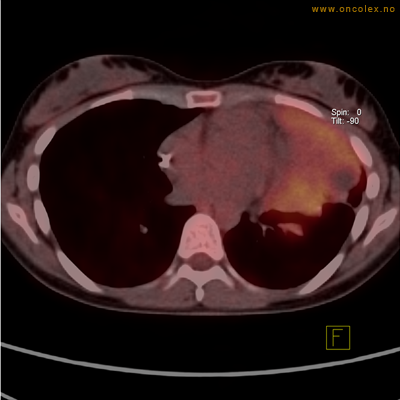

Kraftig opptak i svulst i lunge.

Lungekreft med spredning til lymfeknute i lungehilus.